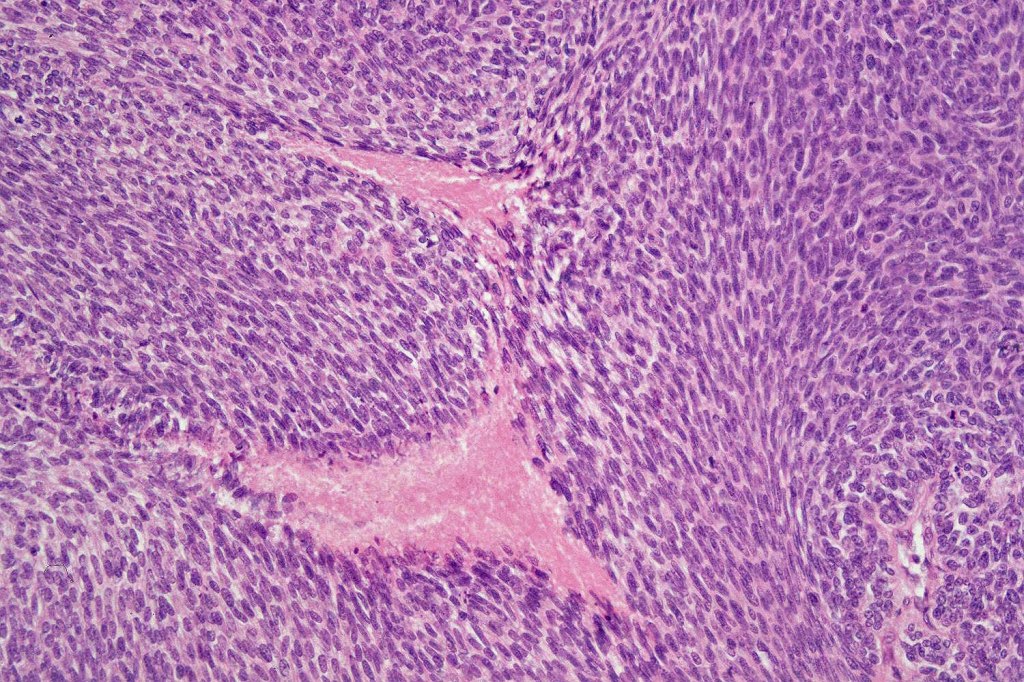

•Well differentiated lobular growth pattern though to a poorly differentiated tumor often showing a diffuse, infiltrating border which may extend into the subcutaneous fat

•Peripheral palisading with retraction artifact and mucin deposition as seen in basal cell carcinoma is not present

•Tumors are composed of an admixture of darkly staining basaloid cells with hyperchromatic or vesicular nuclei and more obvious sebaceous cells with eosinophilic, bubbly, multivacuolated cytoplasm frequently indenting the nucleus (scalloped)

Sebaceous carcinoma from a patient with Muir-Torre syndrome kindly shared by Dr. Antonina Kalmykova.